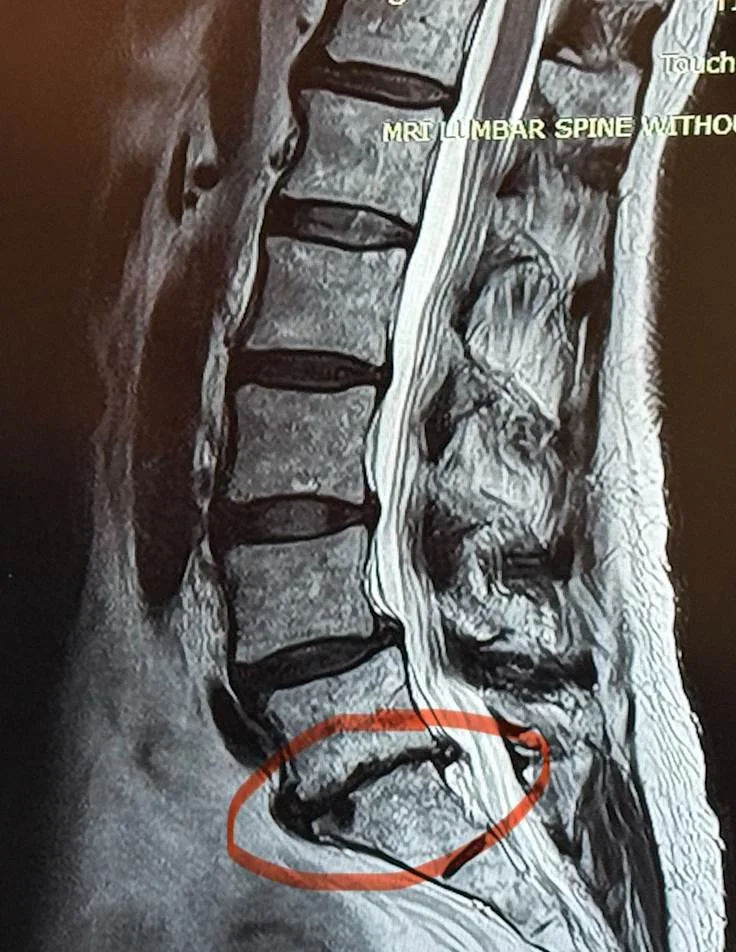

2.. And one disk that has degenerated to bone on bone. (See Photo 2). Compare the red area and the dark spaces above. The red area is collapsed and bone on bone.

Photo 2